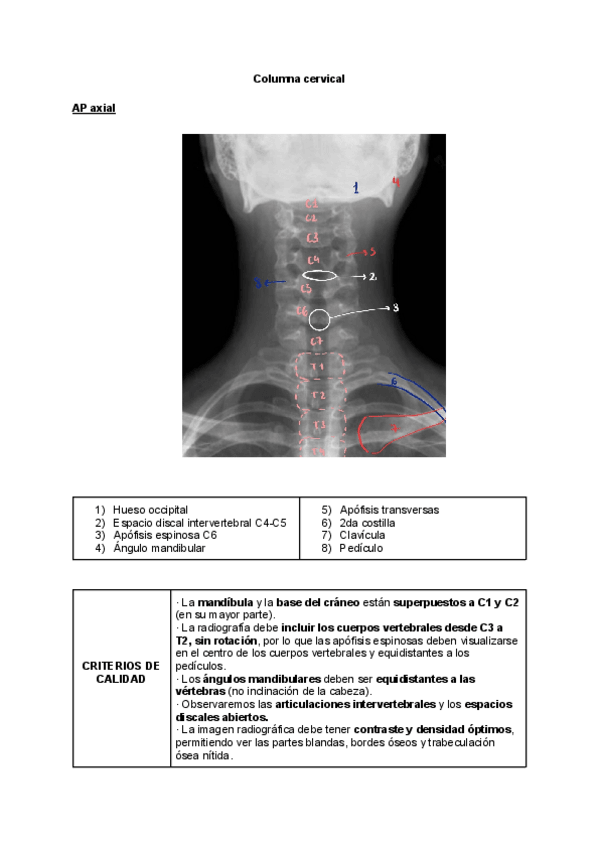

Radiología simple

He publicado nuevos trabajos de Técnicas de Radiología Simple: Radiología simple

Radiologia-simple-Trabajo-Calidad-Ud4-COLUMNA..pdf